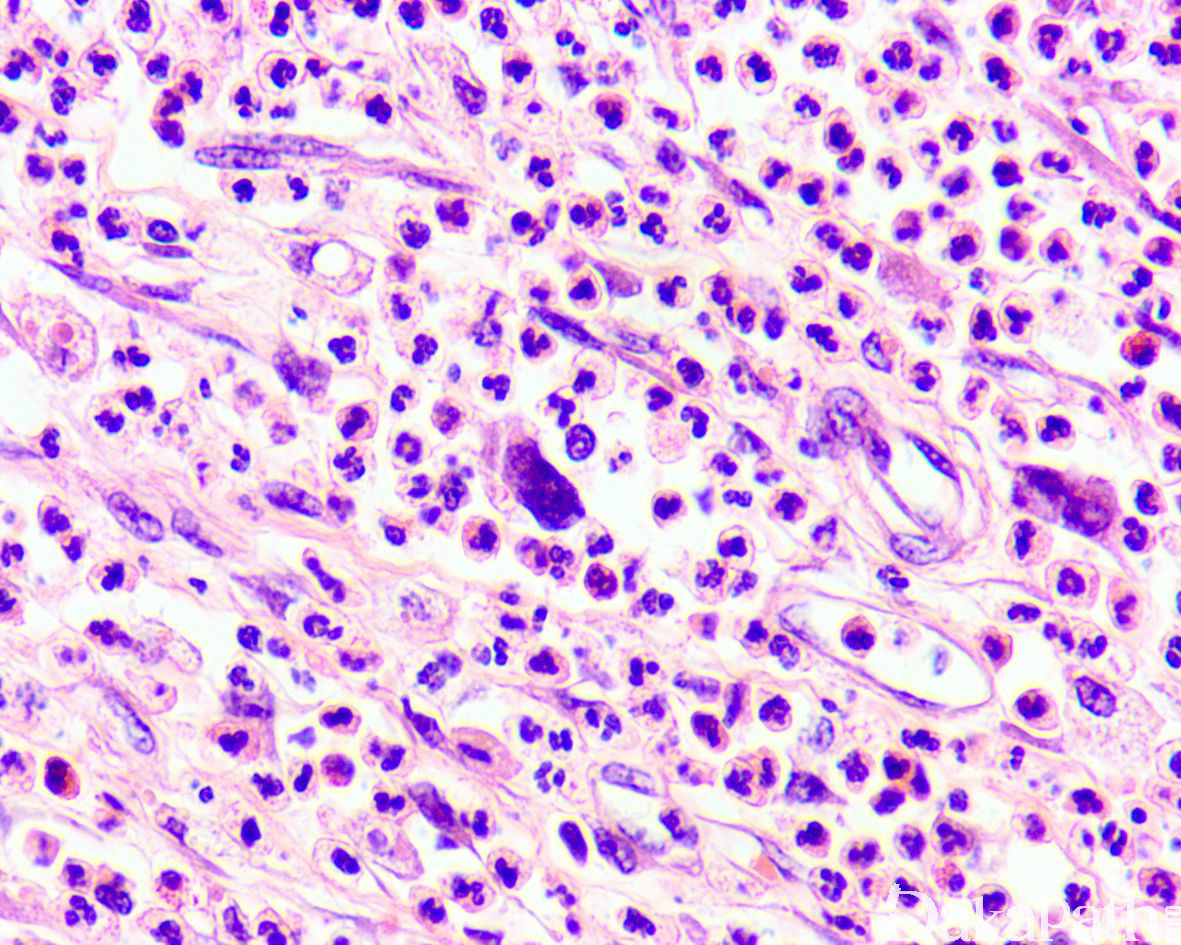

如前所述,DDLPS 组织学上通常表现为 ALT/WDLPS 成分向非脂肪源性的肿瘤成分转化,2 种成分在镜下通常分界较清楚,表现为突然的过渡;但有时可表现为逐渐的过渡或在整个肿瘤内交错的分布(马赛克样的去分化),这一情况尤其在伴有低级别去分化时常见。肿瘤可能部分带假包膜或边界清楚,但至少局部可见推挤状或浸润性边界,后腹膜的 DDLPS 常见累及周围实质器官(如肾脏等)。高分化与去分化成分的比例在不同肿瘤内多少不等,有时候即使在广泛取材的情况下高分化成分也可能完全确如,而去分化成分通常较广泛,但有时也可能仅仅不足 1 cm(又称为微小去分化)。DDLPS 中的 ALT/WDLPS 组织学类型以脂肪瘤样和硬化性为主,而去分化成分大多数表现为高级别去分化特征包括高级别多形性肉瘤样(多形性瘤细胞伴有席纹状排列类似于多形性未分化肉瘤/恶性纤维组织细胞瘤)、高级别梭形细胞肉瘤样(细胞密度较高的梭形瘤细胞伴有交错束状或鱼骨样排列类似于纤维肉瘤)以及少见的高级别圆细胞肉瘤样(弥漫的小蓝圆细胞类似于骨外尤文肉瘤或差分化的滑膜肉瘤)和上皮样特征(弥漫成片的上皮样瘤细胞伴有丰富的嗜酸性胞质或横纹肌样特征类似于转移性癌或恶性间皮瘤),高级别去分化成分通常瘤细胞密度高,间质稀少,核分裂象活跃(> 5 个/10 HPF),但比较于与之类似的肿瘤而言,去分化成分的核分裂象相对较少;坏死较为常见。

约 5%~ 10%的 DDLPS 可显示异源性的间叶性分化,此类肿瘤在过去可能被诊断为恶性间叶瘤,异源性分化常见为骨、软骨、肌样分化以及少见的血管内皮细胞分化。肌样分化表现为横纹肌肉瘤样和平滑肌肉瘤样特点,多发生在后腹膜和睾丸旁等部位,横纹肌肉瘤样 DDLPS 通常为高级别去分化,而平滑肌肉瘤样 DDLPS 既可为高级别也可为低级别去分化。在非常罕见的情况下,DDLPS 可出现异源性的上皮性去分化,除了表现为上皮样瘤细胞特征之外,尚表达细胞角蛋白。尽管大多数 DDLPS 的去分化成分为非脂肪源性肉瘤,少数去分化可为同源性的脂肪肉瘤,组织学表现为低级别或高级别的去分化肉瘤中可见散在或局灶成片的多形性脂肪母细胞,类似于多形性脂肪肉瘤。